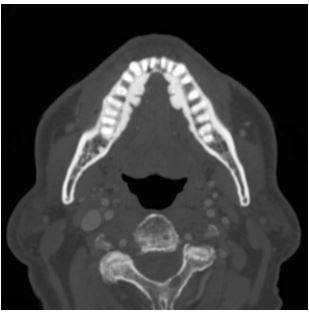

КТ челюсти

Что такое КТ челюсти и что оно показывает

Компьютерный томограф представляет собой кольцо, через которое проезжает стол с лежащим на нем пациентом, когда делается серия последовательных снимков.

Компьютерная томография показывает все необходимые структуры:

тело и все четыре отростка верхней челюсти;

тело и ветви нижней челюсти;

прилегающие костные и полостные структуры - гайморовы пазухи, кости носа.

Вариант нормы на КТ челюсти

Мягкие ткани способны пропускать рентгеновские лучи, и на снимке они отображаются серыми оттенками. Плотные ткани, напротив, поглощают лучи, и на томограмме имеют белый цвет.

Интенсивность затемнения отдельных областей является основным диагностическим показателем, анализируя который, доктор сможет определить наличие или отсутствие патологий в вашем организме.

КТ челюсти и гайморовых пазух

Иногда пациент обращается к стоматологу из-за проблем с зубами, а врач назначает КТ челюсти и гайморовых пазух. Не переживайте, это не попытка навязать дополнительные обследования - часто без сканирования смежных зон просто не обойтись.

Заболевания челюсти и гайморовых (верхнечелюстных) пазух связаны с особенностями их морфологического строения. Корни зубов моляров, а иногда и премоляров (4,5,6,7 и зубы мудрости) проникают в дно пазухи. Поэтому, при возникновении проблем с зубами, это сказывается на состоянии околоносовых пазух.

КТ челюсти и придаточных пазух

То есть ЛОР-заболевания могут быть тесно связаны со стоматологическими проблемами. И иногда требуется консультация двух специалистов: и стоматолога, и оториноларинголога.

Вследствие осложнений стоматологического лечения в пазухе носа могут быть инородные тела, остатки зубов, пломбировочный материал. Если такая неприятность возникла, то не обойтись без КТ, как челюсти, так и гайморовых пазух. Потребуется комплексная терапия - одновременное лечение и зубов, и синусов. В этой ситуации КТ дает панорамную картину, позволяет оценить масштабы проблемы и позволяет специалисту составить правильное лечение.